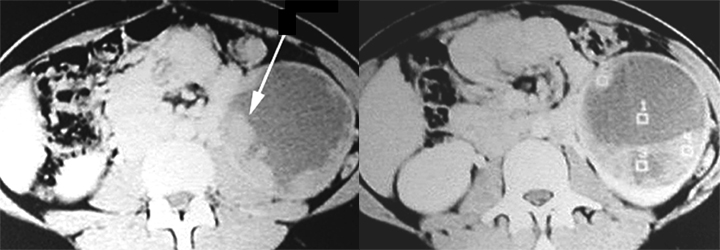

Normal Kidney in CT

Located in retroperitoneum surrounded by fat.

Renal cortex enhances with IV contrast.

In the nephrographic phase the contrast has not been excreted and the renal pelvis appears dark.

Renal pelvis and ureters can be seen as the contrast is excreted by kidneys.

Note the relationship of kidneys

Renal veins drain into IVC. |

Renal Cell Carcinoma

- Arrow: Solid hypodense mass left kidney

- Arrowhead: Normal parenchymal enhancement

- Mass is cystic and solid.

- Tumor nodules are seen arising from the wall of the cyst pointed by long arrow.